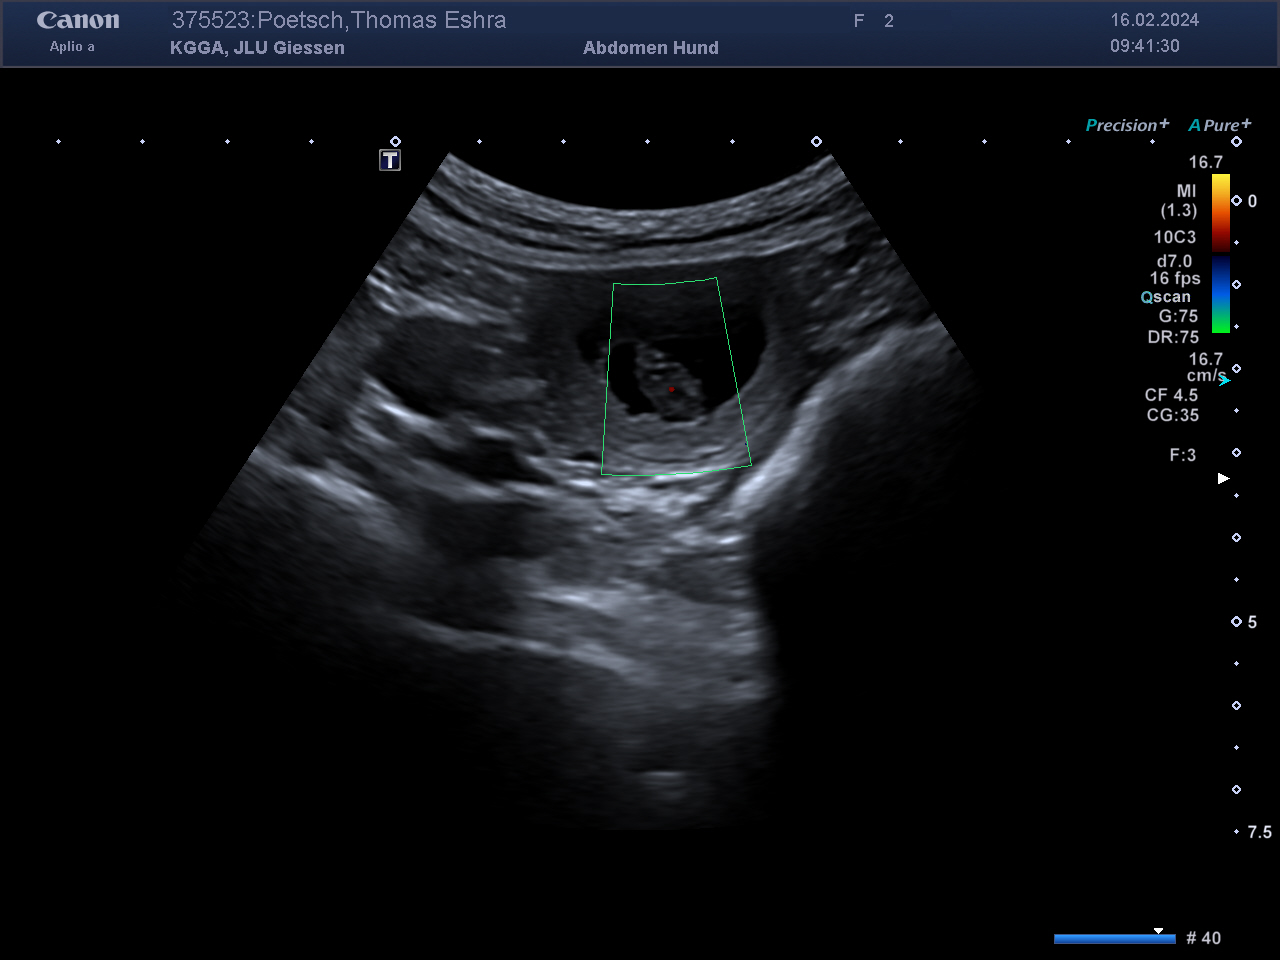

Das Wunder des Lebens! Wir sind super happy, unsere Eshra hat heute Nacht 9 (3/6) gesunde und sehr kräftige Hundebabys auf die Welt gebracht! Ein Riesenwurf mit sehr großen Welpen. Die Geburtsgewichte liegen eng zusammen, alle zwischen 530 und 580 Gramm. Nur der erstgeborene Rüde hat 615 Gramm. Wir sind alle (auch Eshra) von dem…